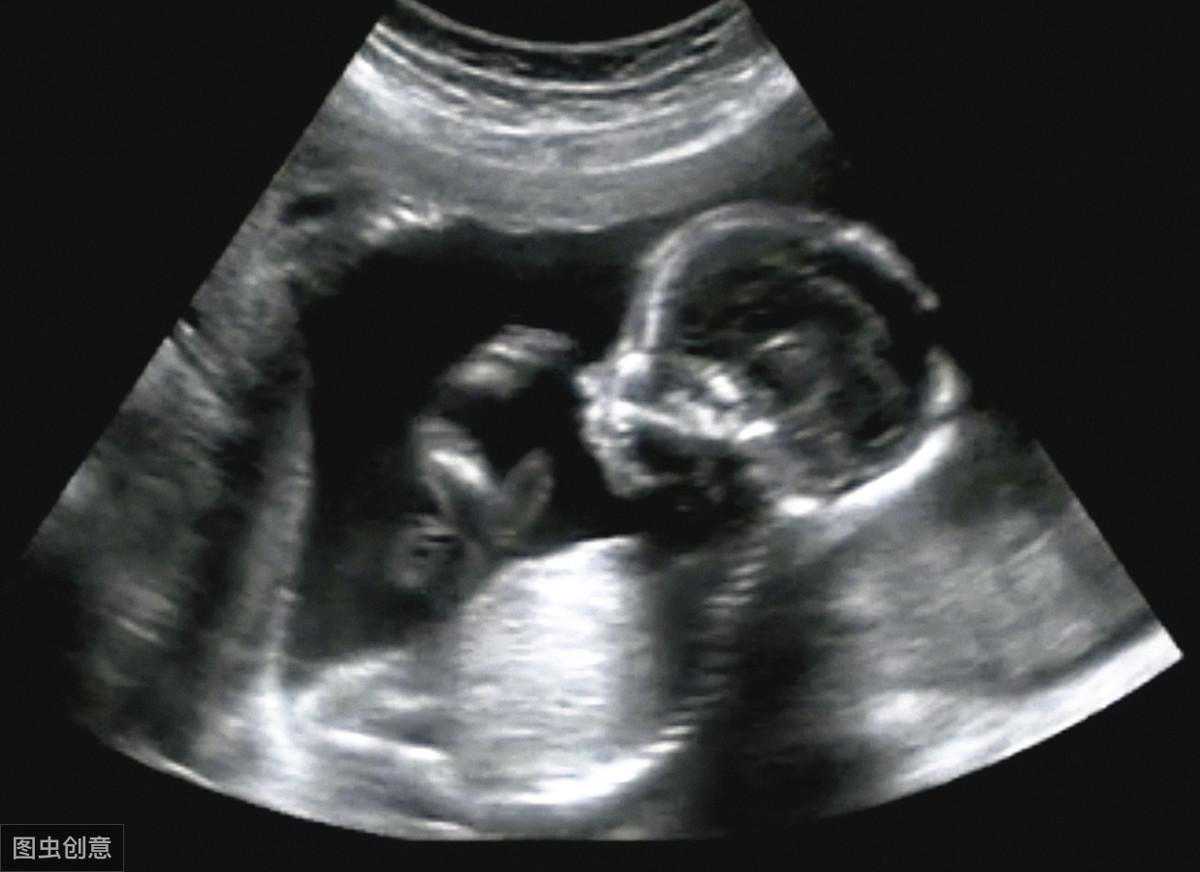

做阴道B超,特别是在怀孕早期做,它的好处是非常多的,因为阴道它是接近了子宫还有卵巢,特别是对于那些比较肥胖的孕妇,腹部脂肪比较厚的孕妇,阴道B超它的成像会比经腹部成像会高,分辨率也比较高,可以看到比较细微的一个病变。在怀孕早期更多的能够观察到它是宫内还是宫外妊娠,宫腔内是否有孕囊,孕囊的大小,宫腔里面到底有没有胚芽或者是胎心搏动等等。

做B超到底有什么好处?做B超的好处远远不止上面所说的,那么做B超的话呢,我在怀孕早期我们可以确定孕囊的位置,那考虑它是宫内还是宫外的,此外我们还可以看到宝宝的胎心搏动;

宝宝在11周到13周+6的时候看到他的那个颈项透明层的厚度用来排查宝宝到底有没有其他畸形;

在孕中期的时候,我们可以做B超大排畸去看一下宝宝的脑部啊,四肢啊,心脏啊等等到底有没有畸形;

在怀孕晚期的时候,我们可以评估宝宝的体重,然后看一下宝宝的一个胎方位啊,到底宝宝方位好不好?羊水足不足,脐血流好不好?来评估它什么时候需要分娩,采取何种方式分娩?